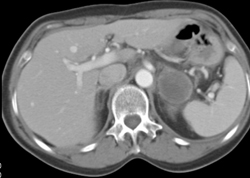

Adrenal Pseudolesion-stomach